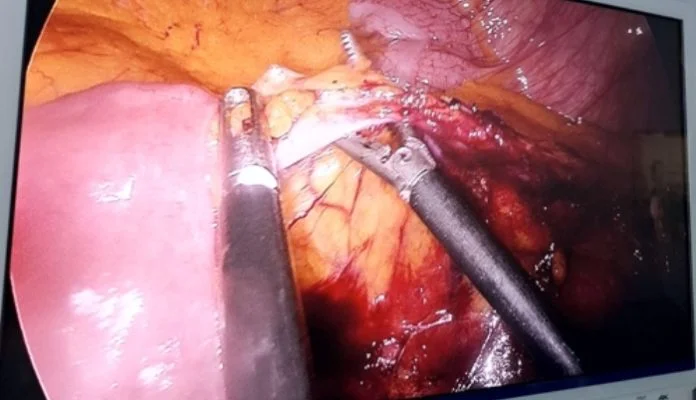

U Kantonalnoj bolnici Zenica 4. septembra 2025. godine uspješno je izvedena zahtjevna i savremena hirurška procedura – laparoskopska niska prednja resekcija rektuma kod pacijenta sa niskim karcinomom rektuma. Riječ je o jednoj od najznačajnijih minimalno invazivnih metoda u liječenju malignih oboljenja rektuma, koja predstavlja važan iskorak u modernizaciji onkološke hirurgije u ovoj ustanovi.

Minimalno invazivni pristup donosi brojne prednosti u odnosu na klasične operativne metode – smanjenu traumu za pacijenta, manje postoperativne bolove, brži oporavak te kraće vrijeme hospitalizacije, uz potpuno očuvanje onkoloških principa liječenja. Na taj način značajno se podiže kvalitet zdravstvene usluge i povećava sigurnost pacijenata.

Operaciju je izveo tim stručnjaka Kantonalne bolnice Zenica:

• Operater: dr Elvir Bešić, specijalista opće hirurgije

• Asistent: dr Mahir Omanović, specijalista opće hirurgije

• Anesteziolozi: dr Jamina Šabić i dr Elis Vujić

• Instrumentar: Edin Isaković

Izvođenjem ovakvih zahvata, Kantonalna bolnica Zenica potvrđuje svoju posvećenost kontinuiranom stručnom razvoju, uvođenju najsavremenijih medicinskih procedura i unapređenju kvaliteta liječenja pacijenata oboljelih od malignih bolesti.

Kako ističu iz bolnice, ovaj uspjeh je rezultat timskog rada i predanosti zdravstvenih profesionalaca, te predstavlja dodatni korak ka daljoj modernizaciji zdravstvene zaštite u ovoj ustanovi.